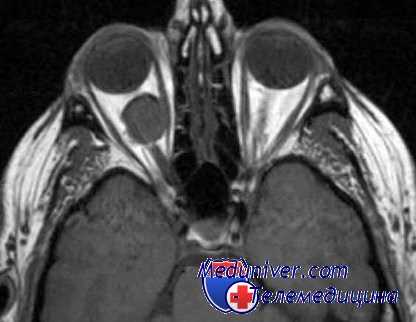

Клиническая картина мукормикоза и аспергиллеза наряду с общими признаками имеет и некоторые отличия. Общим следует признать сочетанное поражение орбиты и параназальных синусов (первичный микоз орбиты) или риносиноорбитальное поражение (вторичный микоз орбиты). По распространенности процесса выделяют три клинические стадии заболевания. Поражение околоносовых пазух типично для I стадии заболевания; для II стадии характерно вовлечение в патологический процесс носа и орбиты (риноорбитальное поражение); III стадия свидетельствует о распространенности процесса вплоть до головного мозга (риносиноорбитоцеребральное поражение). Головная, норой невыносимая боль и боль за глазом также типичны для обеих групп поражения орбиты.

При мукормикозе картина начинается всегда остро с быстро развивающимися признаками воспаления в орбите по типу целлюлита. Как правило, у всех больных мукормикозом орбиты наблюдают тактильную болезненность на соответствующей половине лица, в периорбитальной области. Кожа век отечная, гиперемирована, резкий, быстро нарастающий экзофтальм с красным хемозом. Глаз неподвижен, репозиция его невозможна. Нарушение гемодинамики глаза приводит к развитию инфаркта сетчатки с резким снижением зрения.

Указанные изменения развиваются в результате нарушения гемодинамики, обусловленной не только увеличением объема мягкотканого содержимого орбиты, но и патоморфологическими факторами. Патогистологические исследования удаленной из орбиты ткани (экзентерация орбиты по поводу мукормикоза) у соматически здоровых лиц показали наличие обширного рассеянного асептического воспаления с небольшими ограниченными кровоизлияниями и внутрисосудистыми тромбами. Орбитальный или синоорбитальный мукормикоз достаточно быстро распространяется в полость черепа, что сопровождается быстро развивающимся параличом черепно-мозговых нервов.